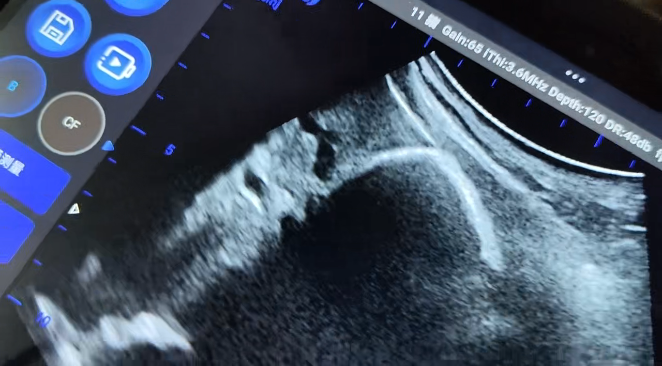

在现场演示中,BXL-V80 表现出了良好的图像清晰度与操作便捷性,获得了厂区技术人员的认可。